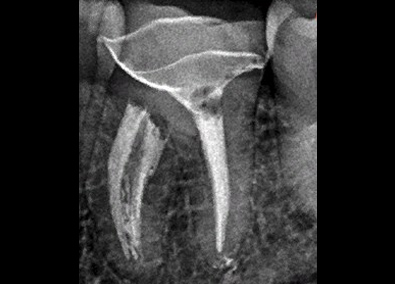

Лечение каналов зуба

Фото ДО

Фото ПОСЛЕ

Наведите для просмотра